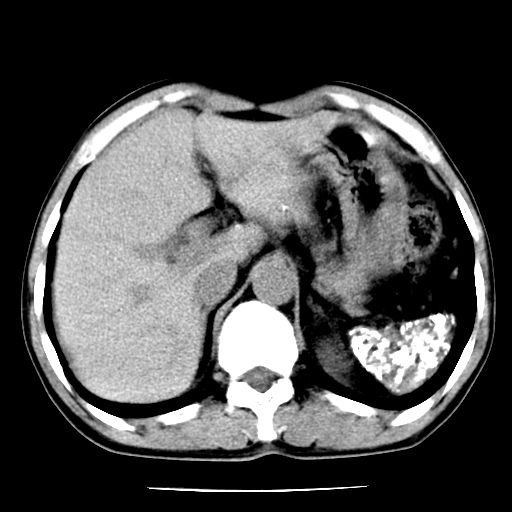

男,59岁,“结核性胸膜炎”30余年,胸部经常疼痛,多次x检查提示“肺部”炎症。腹部疼痛5日,b超提示:“肝内短管结石,余显示不清,建议进一步检查。”

两肺结核并右侧胸腔积液;脾脏、腹腔及腹膜后淋巴结结核[陈旧性];肝内胆管结石

胸部腹部都是结核(双肺。纵隔淋巴结,肝脏,脾脏,肠系膜)

两肺结核并右侧胸腔积液;脾脏、腹腔及腹膜后淋巴结结核[陈旧性];肝内胆管结石。直肠息肉?